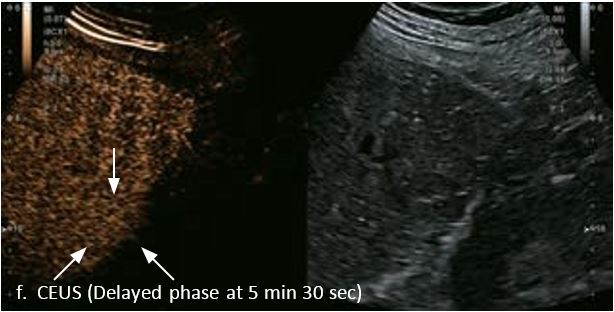

Оцінка результатів лікування ГЦК

Проведено повторне обстеження 79-річного чоловіка з цирозом печінки В, ускладненим ГЦК, після транс-артеріальної хіміоемболізації (ТАХЕ). Було виявлено нове ураження, розташоване поруч з ураженням після ТАХЕ. На сірошкальному зображенні чітко видно нове ураження, але складно виявити рецидив ГЦК в зоні ураження після ТАХЕ. За допомогою кольорового картування SMI (cSMI) можна побачити розвинену судинну мережу всередині нового вогнища ураження. Для оцінки результату лікування було виконано CEUS. За допомогою CEUS можна легко дослідити як нове ураження, так і рецидив ГЦК у вогнищі ураження після TACE. Нове ураження демонструє гіперпосилення артеріальної фази і відсутність вимивання до 5 хвилин, отже, це ураження LI-RADS 4, ймовірна ГЦК за критеріями LI-RADS. Підживлюючі судини можна чітко спостерігати в ранній артеріальній фазі. Для ураження після TACE, більша його частина не підсилюється, однак, в артеріальній фазі спостерігається ділянка гіперпосилення у верхній частині лікованого ураження, що вказує на рецидив ГЦК.

Малюнок 10